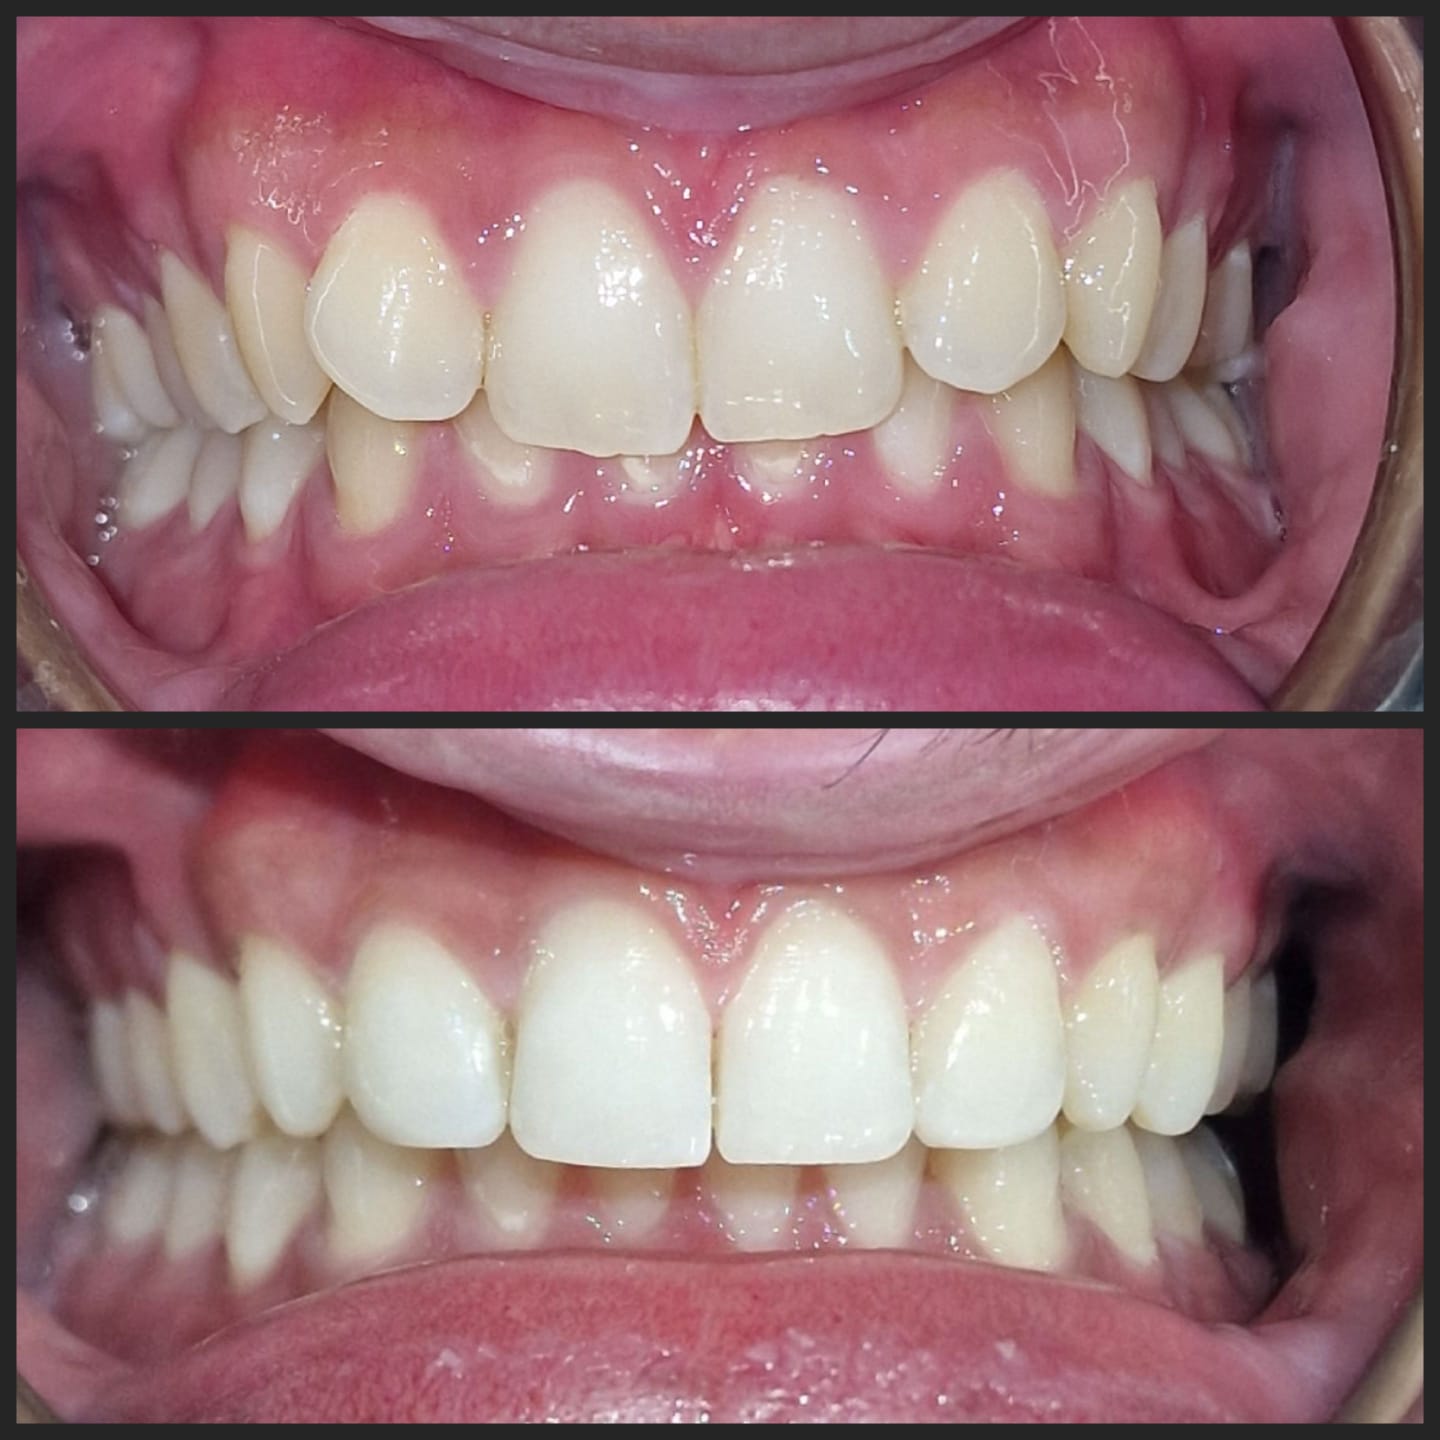

Invisalign is a clear alternative to traditional metal braces, offering a discreet and convenient way to achieve a straighter smile. Unlike traditional braces, Invisalign aligners are removable and nearly invisible, allowing you to eat, drink, and live your life without restriction. With Invisalign, you can straighten your teeth without the hassle and self-consciousness of metal braces.

Invisalign is also a highly effective and efficient way to achieve a straighter smile. Using advanced technology, Invisalign creates a personalized treatment plan that moves your teeth into place in a precise and predictable way. With Invisalign, you can enjoy a straighter, healthier smile in as little as 12-18 months, with fewer orthodontist visits and less discomfort than traditional braces. Plus, Invisalign aligners are smooth and comfortable, reducing irritation and discomfort.

Invisalign is a well-known system for straightening teeth in the most discreet way. It works by using a series of clear aligners that fit comfortably over the teeth to gently move them into the desired position over time. There are no fixed brackets or wires used, in fact, the aligners are completely removable.